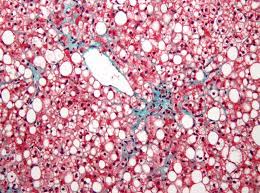

지방간(Non-Alcoholic Fatty Liver Disease, NAFLD)는 간 내에 지방이 비정상적으로 축적되는 만성적인 질환입니다. 이 질환은 주로 알코올 소비량이 낮거나 없는 사람들에서 발생하며, 지방이 간세포에 과도하게 축적되어 간의 정상 기능을 저해하는 특징을 가지고 있습니다.

1. 비알코올성 지방간병증 (Non-Alcoholic Fatty Liver, NAFL): 이 하위 유형은 알코올 소비량이 낮거나 없는 사람들 중에 나타나며, 주로 비만, 당뇨병, 고지혈증과 관련이 있습니다. NAFLD는 간에서 지방이 축적되지만 염증과 파열이 없는 비염증성 상태입니다.

2. 비알코올성 지방간염 (Non-Alcoholic Steatohepatitis, NASH): NASH는 NAFLD 중에서도 더 심각한 형태로, 지방 축적 외에도 간세포 염증 및 손상이 동반됩니다. NASH는 간세포의 염증과 손상이 진행될 경우 간 경화(간 섬유화)로 진행될 수 있으며, 이는 간 기능의 저하와 심각한 합병증을 유발할 수 있습니다.

6. 간 생검: 가장 정확한 NAFLD 진단을 위해서는 간 조직을 직접 검사하는 간 생검(간 조직 검사)이 필요할 수 있습니다. 그러나 간 생검은 치료나 합병증의 위험을 내포하므로 일반적으로 마지막 수단으로 고려됩니다.